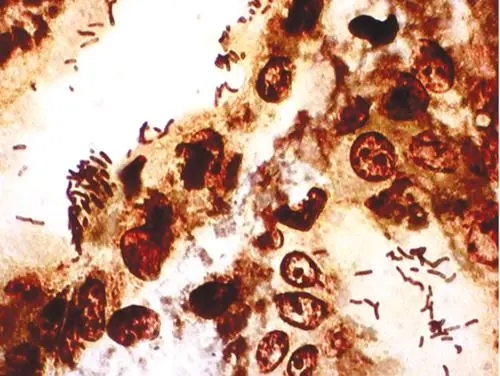

番红o染色:番红(也称作番红O或基本红2)是个用在组织学和细胞学的生物染色剂。番红在一些染色的实验计划表中用作复染剂,将所有的细胞核染成红色。这在革兰氏染色和内孢子染色都是典型的复染剂。它也可以被用

番红o染色:番红(也称作番红O或基本红2)是个用在组织学和细胞学的生物染色剂。番红在一些染色的实验计划表中用作复染剂,将所有的细胞核染成红色。这在革兰氏染色和内孢子染色都是典型的复染剂。它也可以被用来检测软骨、黏蛋白和肥大细胞的颗粒。